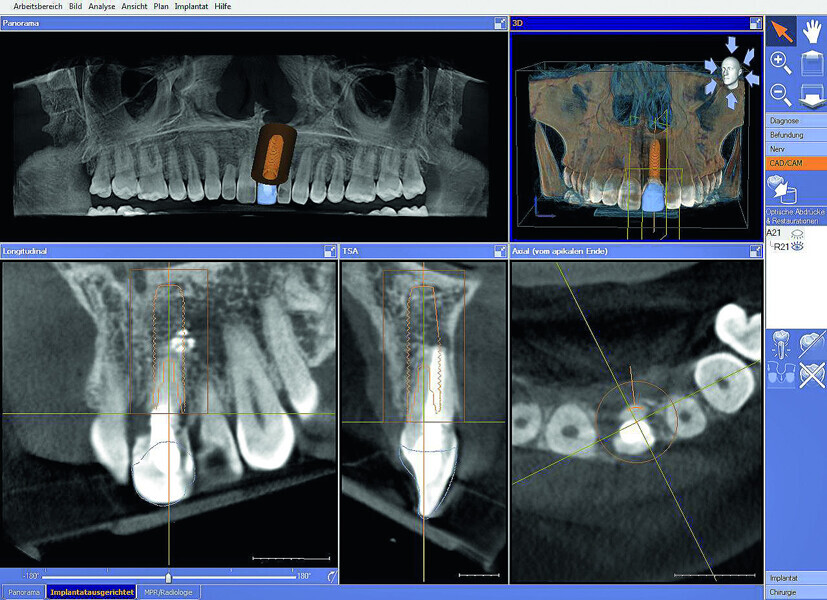

Fig. 3: The initial situation in 3-D in the Sidexis 4

imaging software (Dentsply Sirona) showed good apical bone substance with the possibility of immediate implantation.